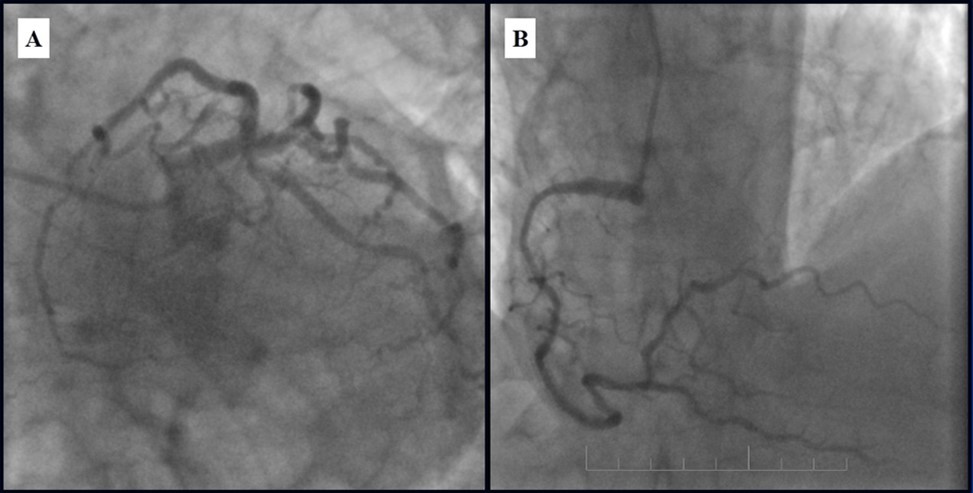

Angiography revealed rare anatomical variation LMCA quadrifurcation (Figure 1, Figure 2), 50% stenosis of the distal part of the LMCA, 40% stenosis of the ostial segment of left anterior descending (LAD) artery and diffuse prolonged 70-75-95% stenosis in mid-segment (Figure 3), 75% stenosis of the ostial segment of the circumflex (CX) artery, 75% stenosis of the ostial segment of the first marginal branch (OM1), 75-90% stenosis of the proximal segment of the intermediate artery (IMA), prolonged diffuse severe 90-95% stenosis of mid-segment of the right coronary artery (RCA) (Figure 4).

Figure 1.Quadrifurcation of the left main coronary artery

Figure 3.Prolonged diffuse severe 90-95% stenosis of mid-segment of the right coronary artery. A - Left anterior oblique 45° projection; B – Right anterior oblique 45° projection.

Figure 4.A - 50% stenosis of the distal segment of the LMCA; B - 70-75-95% stenosis in mid-segment of the LAD.